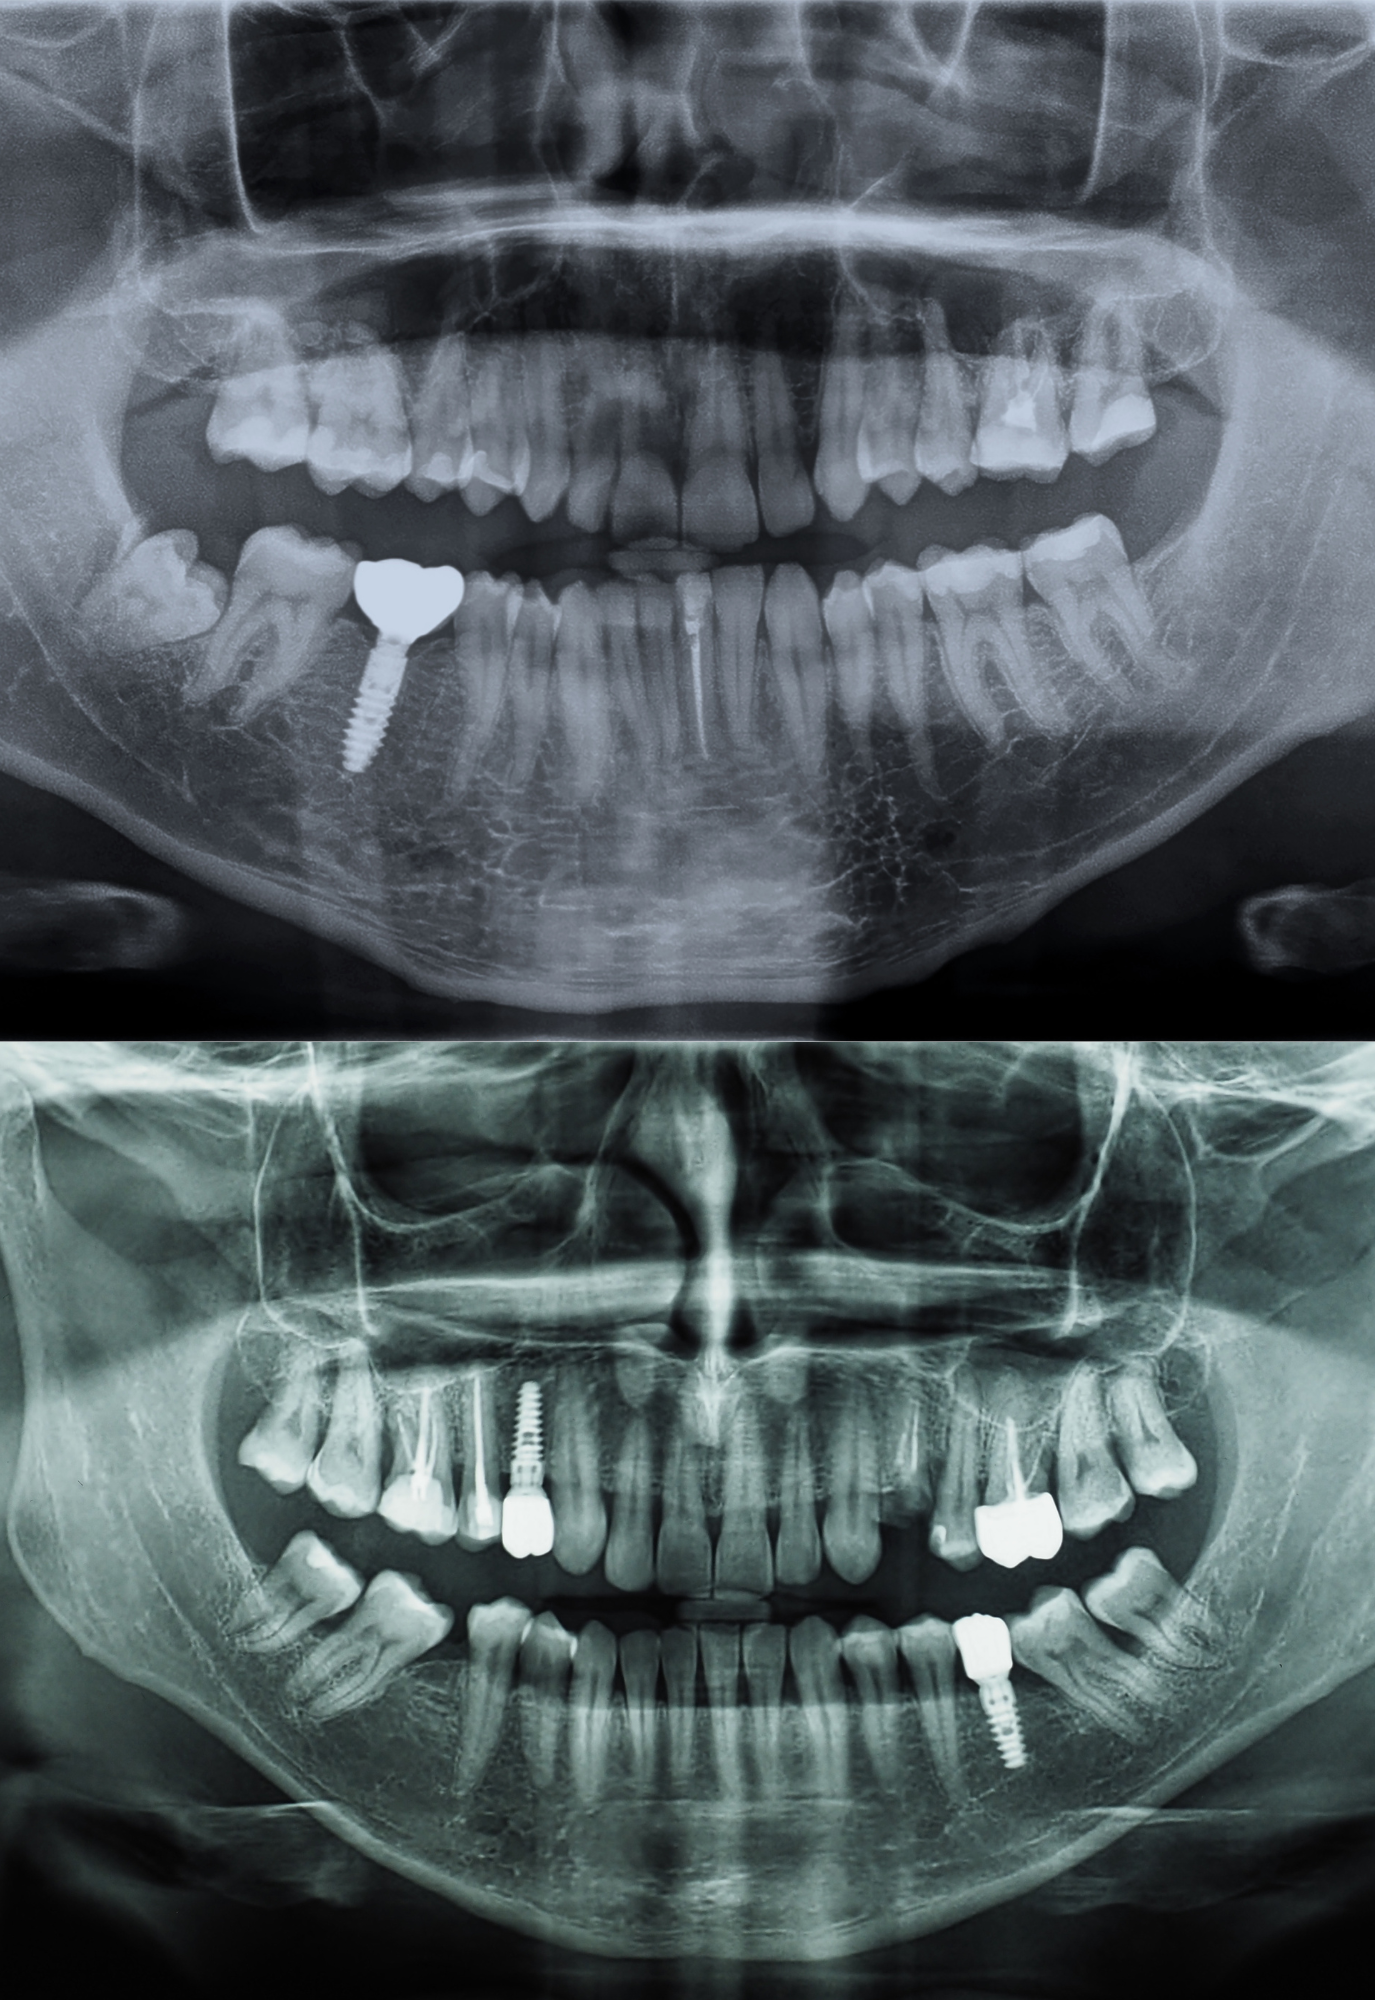

dental implant x-ray

Dental implants are titanium posts that replace the root of a missing tooth. They fuse with your jawbone and support a natural-looking crown, bridge, or denture.